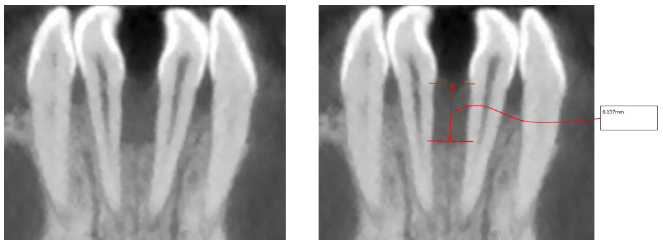

2.3. Individual Tooth Model Extraction

The individual tooth anatomies are not so simple to extract from tomographic data because of similar grey intensity values of the tooth root and surrounding bone tissue. Slice-by-slice segmentation procedures are commonly used for this purpose, but this can result in processing hundreds of slices in order to obtain segmented models, thus leading to time-consuming procedures. In this case, DICOM images were processed by adopting the methodology introduced in the paper by Barone et al. [10]. This method is based on processing a subset of images (reformation images) for each tooth on the basis of anatomy-driven considerations. The reformation images allowed us to easily obtain the tooth geometry by using a limited set of 2D curves representing the contour of the tooth in each image. Indeed, four reference planar sections were automatically obtained. These reference sections were used to outline the tooth by tracing four different 2D curves that represented the tooth contours (Fig. 4a). The four contours were used to automatically extract a series of closed curves on each slice perpendicular to the tooth axis (transverse slice) (Fig. 4b).

This methodology allowed us to rapidly extract the geometry of a full tooth by means of manually processing a few automatically extracted images from CBCT data. The processing time was significantly lowered compared to common manual standard methods.